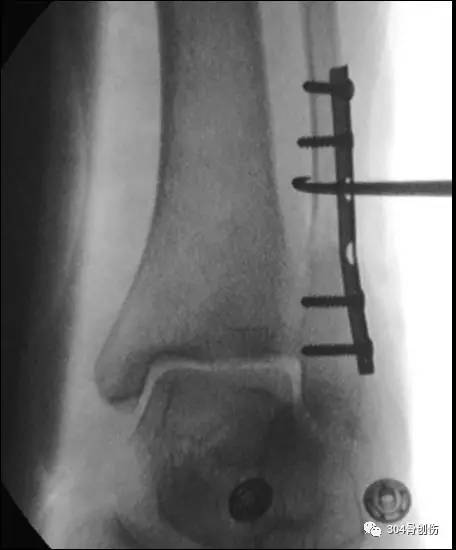

术中影像诊断新方法

Chertsey 试验

踝部骨折术中如何判断下胫腓分离程度?最常用的就是“拉钩试验(Cotton test)”,透视观察下胫腓之间距离。当下胫腓固定后,胫腓骨远端位置是否妥当?拉钩试验难以评判。最好的方法就是术中CT检查,但目前不是所有的手术室均有术中CT,多是靠术后CT检查后判断,一旦发现下胫腓位置关系不正确,相当一部分需要重新翻修,增加了患者的痛苦,也增加了手术感染风险。简单可靠的评估方式亟需在临床上推广。

术中判定下胫腓稳定

常用的方法-拉钩试验

部分病例术后发现下胫腓关系错误

常常需要再次手术翻修调整

英国Boyd 等人提出在术中判断下胫腓联合损伤或腓骨复位情况的新方法-Chertsey 试验,该文发表在Injury 杂志。

Chertsey(切特西)位于英格兰萨里郡兰尼米德区的一个集镇,位于泰晤士河畔。该文作者所在医院位于该地区,故名“Chertsey 试验”

Boyd 文献-Chertsey 试验

Robert P.R., Syed Zuhair Nawaz, Arshad Khaleel.A new assessment for syndesmosis injury – The ‘Chertsey test’Injury. 2016 Jun;47(6):1293-6.